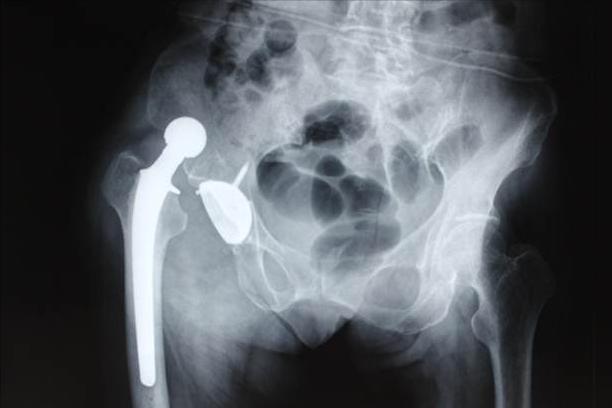

生活和工作方式的改变让越来越多的人患上慢性关节病,体重增加、运动缺乏和不良姿势是主要原因。慢性关节炎是致残性疾病中最常见的一种,晚期患者会面临关节畸形和关节功能丧失,这时候保守治疗基本上没什么效果,患者要考虑置换人工关节。近年来,人工关节置换术的手术量逐年上升,但仍有许多患者对其保持怀疑,尤其担心副作用,今天我们就来看看有哪些副作用!

大血管损伤的概率是很小的,但不可不防,因为一旦发生就会威胁患者的生命,尤其是在翻修手术中。神经损伤也是常出现的,像髋关节置换容易损伤股神经、坐骨神经,膝关节置换可以损伤腓总神经,通常神经损伤在一年后能基本恢复。

主要有两种原因,一种是手术原因,如翻修手术、手术入路不当、小切口手术、假体使用不当等,另一种是非手术原因,主要是高龄、女性、骨质疏松、高BMI、既往手术史、创伤等。这里要着重强调的是,高龄女性患者要重点预防骨质疏松,绝经期骨质疏松及激素等药物的使用,都会增加骨质疏松及假体周围骨折的风险。

08 / 术后假体脱位

术后假体脱位的发生率可能介于1%~5%之间,原因也有手术原因和非手术原因之分。手术原因主要包括假体设计、假体选择、手术入路、软骨组织处理等,非手术原因主要包括高龄、女性、神经或精神功能异常、生活护理不当、原发疾病等。